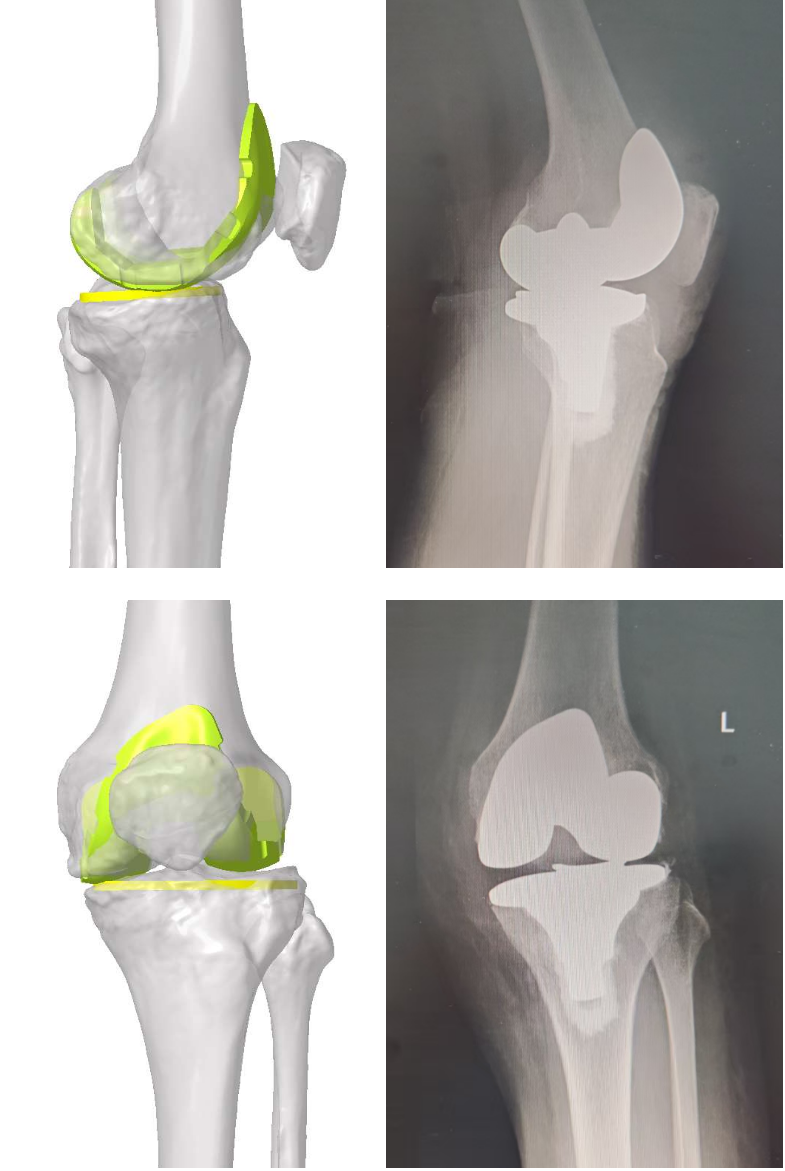

术前模拟与术后对比

通过术后X光片与术前设计的模拟图的对比可以看出,手术结果符合术前规划设计,再次印证了灵犀PSI导板在数字化精准医疗领域的优异表现。